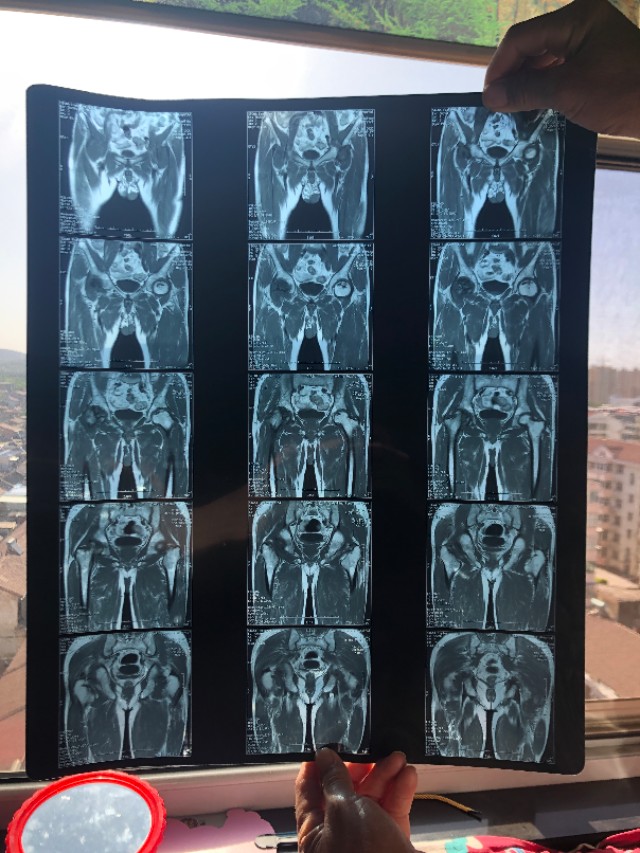

去年10月开始疼痛持续的时间比较久,他还是没去看,平时就靠止疼药维持,过年的时候才给我们讲,然后去医院抓了几副中药喝了,也没起什么作用,后来因为疫情封村,也就没去检查,直到前几天才去检查,做了核磁共振后,结果讲股骨头坏死。

请各位条友们帮忙看看,这个还需要做什么样的检查?大概是因为什么原因引起的?后续治疗方法是什么?谢谢!